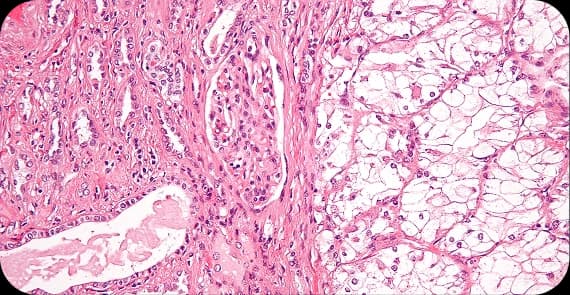

Most kidney cancers begin in the lining of tiny tubes within the kidney, though other forms can arise in different kidney structures.

Kidney cancer is not a single disease. There are different types of kidney cancer, each with its own distinct biological behaviour and treatment considerations.

The most common type in adults, arising from the kidney’s filtering tubules.